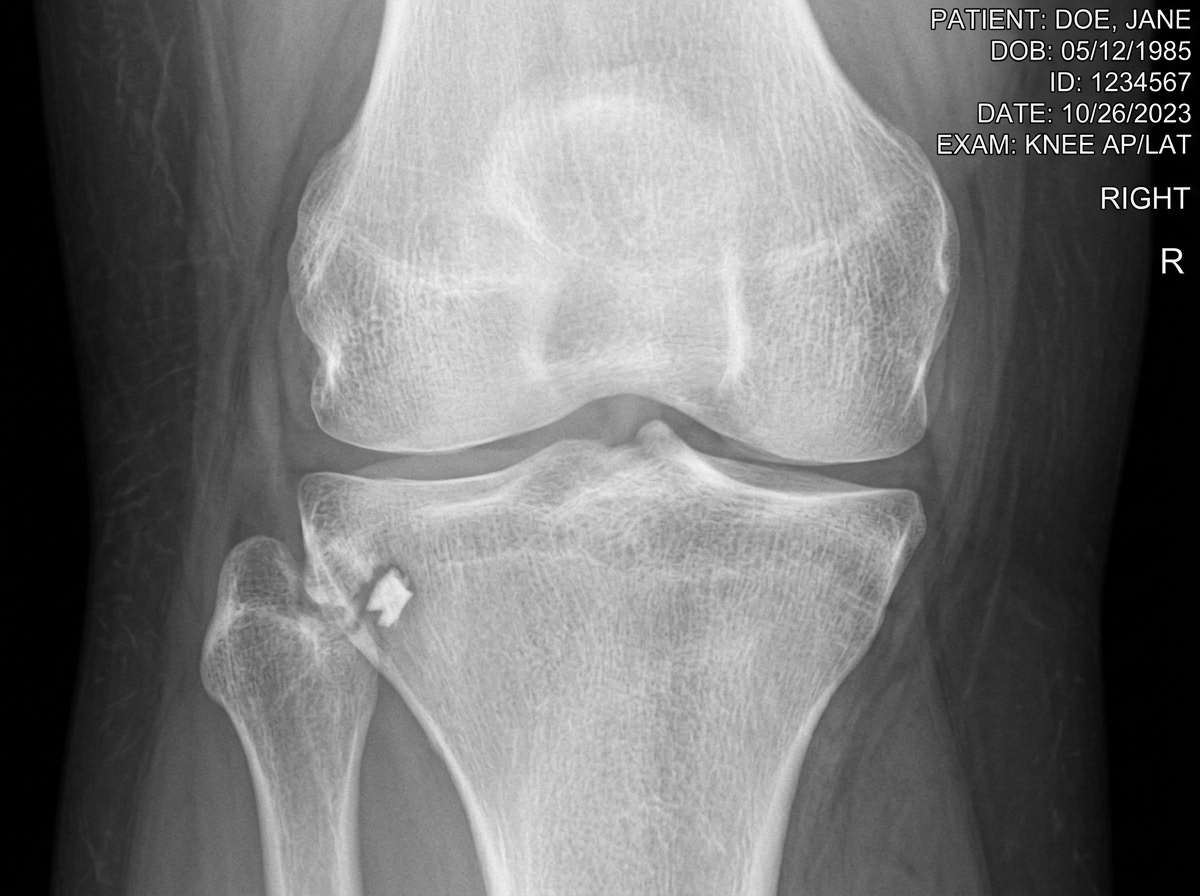

The Segond Fracture: A Red Flag for ACL Injury

The Segond fracture is perhaps the most famous "sidekick" to an ACL injury. Named after Paul Segond, who described it in 1879, it is a small avulsion fracture of the lateral tibial plateau.

Why do we care so much about a tiny sliver of bone? Because it is considered pathognomonic for an ACL rupture. This means if we see a Segond fracture on your X-ray, there is a 75% to 100% chance you also have a torn ACL. It occurs when the tension on the lateral side of the knee—specifically involving the anterolateral ligament (ALL)—becomes so great during a twisting motion that it rips a piece of bone right off the tibia.

Identifying this "red flag" early helps us provide a more accurate diagnosis of knee ligament injuries before you even step into the MRI suite.

Diagnostic Imaging: Beyond the Standard X-Ray

If you go to an urgent care in Bastrop or Lockhart after a knee injury, they will likely start with an X-ray. While X-rays are great for seeing a Segond fracture or a displaced tibial eminence, they are notoriously bad at seeing the most common fractures associated with ACL tears.